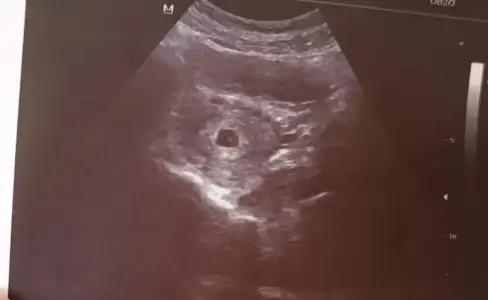

Ölçüm yaptığı şeyKızlar merhaba. Kesede görünen iki beyaz bokta ile ilgili bilgisi olan var mı ?

Teşekkür ederim hiç birsey soylemedi yolk kesesiyle ilgili valla bende gördüm merak ettim bak simdiMaşallahben içinde yolk kesesini de gördüm sanki, yanlış mı görüyorum

Benim ki de öyle çünkü ondan yolk dedimTeşekkür ederim hiç birsey soylemedi yolk kesesiyle ilgili valla bende gördüm merak ettim bak simdi

Seninkinin içindeki o küçük şey yolk kesesimiymis doktor mu söyledi bana niye bisey demedi ki yaBenim ki de öyle çünkü ondan yolk dedim![]()

Bende bugün ilk defa kese gördüm yolk çok belli belirsizdi. Kaç haftalık şuan kesenizin büyüklüğü ne?Benim ki de öyle çünkü ondan yolk dedim![]()